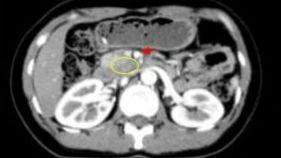

Ngày 23/12, Bệnh viện đa khoa Vĩnh Long cho biết, bệnh viện vừa thực hiện thành công ca phẫu thuật nội soi cắt bỏ hoàn toàn khối u mạc treo ruột kích thước khổng lồ (nặng hơn 6kg) cho bệnh nhân nữ lớn tuổi. Đây là ca bệnh phức tạp, khẳng định năng lực chuyên môn sâu về kỹ thuật phẫu thuật nội soi tại bệnh viện.